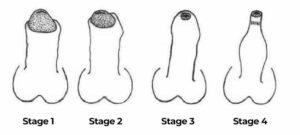

اعدادوشمار بتاتے ہیں کہ 80% مرد اپنی جسمانی صحت سے مطمئن نہیں ہوتے۔ لیکن 35 سال کی عمر کے بعد مردوں کو ایک اور سنگین مسئلے کا سامنا کرنا پڑتا ہے: عمر کے ساتھ پٹھوں کی کمزوری، جو ہر سال 2-3% کم ہوتی ہے۔ بدقسمتی سے، یہ مسئلہ مردانہ صحت کو بھی متاثر کرتا ہے، کیونکہ اس کا 50% حصہ پٹھوں پر مشتمل ہوتا ہے۔ وقت کے ساتھ یہ کمزوری بڑھتی جاتی ہے:

اگر آپ کی صحت کمزور ہے تو آپ اپنے رشتوں کو مضبوط نہیں رکھ سکتے! یہ ثابت شدہ حقیقت ہے! ابھی اس مسئلے کو حل کریں، ورنہ بعد میں بہت دیر ہو جائے گی! میں آپ کو بتاؤں گا کہ عمر کے ساتھ ہونے والی کمزوری سے کیسے بچا جا سکتا ہے۔